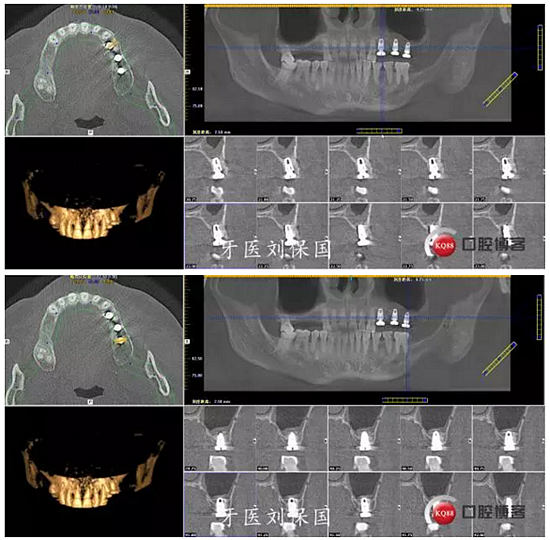

4.六個月后二期CT: